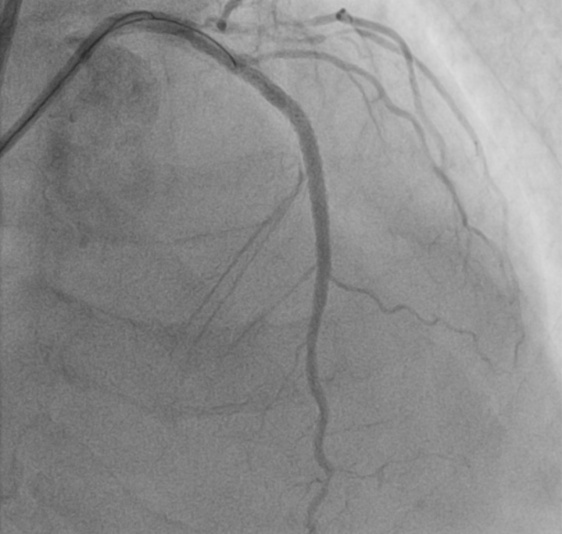

时间就是生命,每一分每一秒都关乎患者安危。抵达医院后,心血管内科在刘学波主任的指挥下迅速响应,医护人员第一时间投入到紧急救治工作中。王明的治疗难度极大,因多年患有糖尿病,心脏三根主要血管均存在重度弥散性钙化病变,外周血管状况也差,且肾功能不全、贫血。经过纠正心衰治疗病情相对稳定后,1月13日,在前期充分的药物治疗基础上,刘学波、来晏、姚义安、钱军等医生对患者行冠脉造影术,提示心脏三根冠脉均存在重度狭窄。其中最重要的左前降支为重度钙化病变,并且术中患者血压偏低,医护人员当机立断,为患者植入主动脉内球囊反搏(IABP),针对严重钙化的血管,来晏主任医师精准运用冠脉内冲击波碎石术(震波球囊)等专业技术破解治疗难题,成功在左前降支植入支架,有效疏通狭窄血管,手术全程顺利,为患者生命安全奠定坚实基础。

支架术后